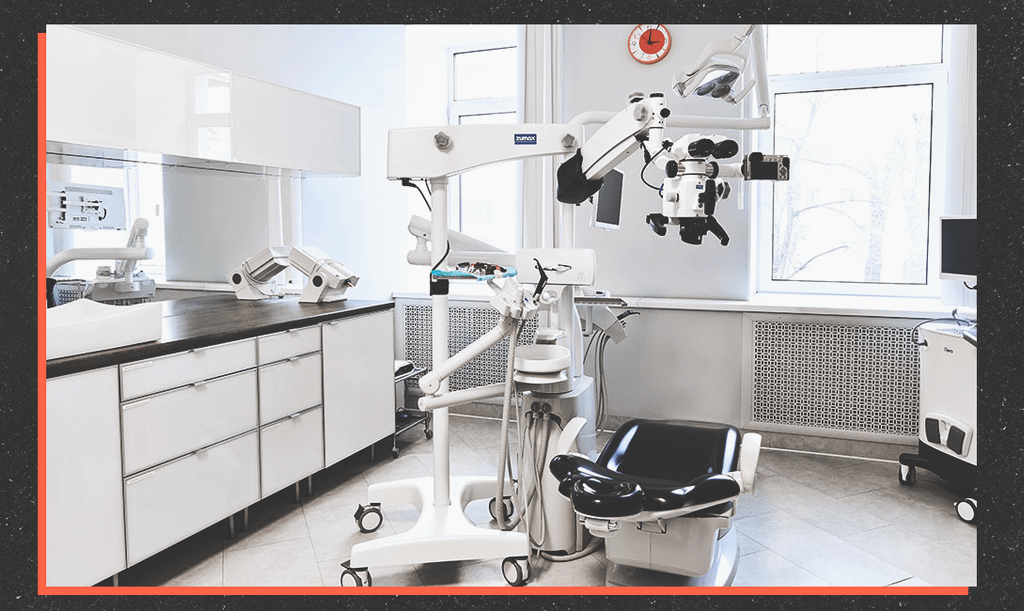

В каждом кабинете клиники есть стоматологический микроскоп для детального обследования. С его помощью удаётся увеличить место осмотра в 30 раз и выявить любую зубную болезнь ещё на стадии развития. Собственная зуботехническая лаборатория позволяет максимально быстро изготавливать различные индивидуальные конструкции – коронки, виниры, протезы и ортодонтические аппараты.